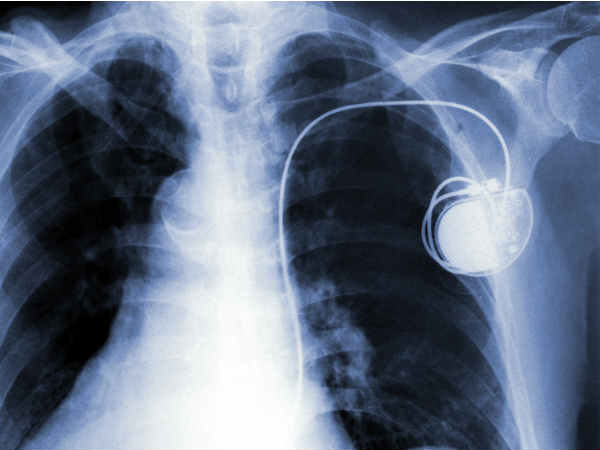

പേസ്മേക്കര്: അറിയേണ്ട കാര്യങ്ങള്

ഹൃദയനിരക്ക് കുറവുള്ള രോഗികളുടെ ഹൃദയ പേശികളിലേക്ക് ഇലക്ട്രിക് തരംഗങ്ങള് അയച്ച് കൃത്രിമമായി ഹൃദയമിടുപ്പ് നല്കുന്നതിന് വേണ്ടി ഉപയോഗിക്കുന്ന വളരെ ചെറിയ ഉപകരണമാണ് പേസ്മേക്കര്. 25 മുതല് 35 ഗ്രാം ഭാരമെ ഇതിന് ഉണ്ടാകു.

ഇടതോ വലതോ തോളെല്ലിന്റെ താഴെയായി ചര്മ്മത്തിനും കൊഴുപ്പിനും അടിയിലായാണ് പേസ് മേക്കര് സ്ഥാപിക്കുന്നത്. പേസ്മേക്കറിന്റെ ലീഡ് ഞരമ്പ് വഴിയാണ് ഹൃദയപേശികളുമായി ബന്ധിപ്പിക്കുന്നത്.